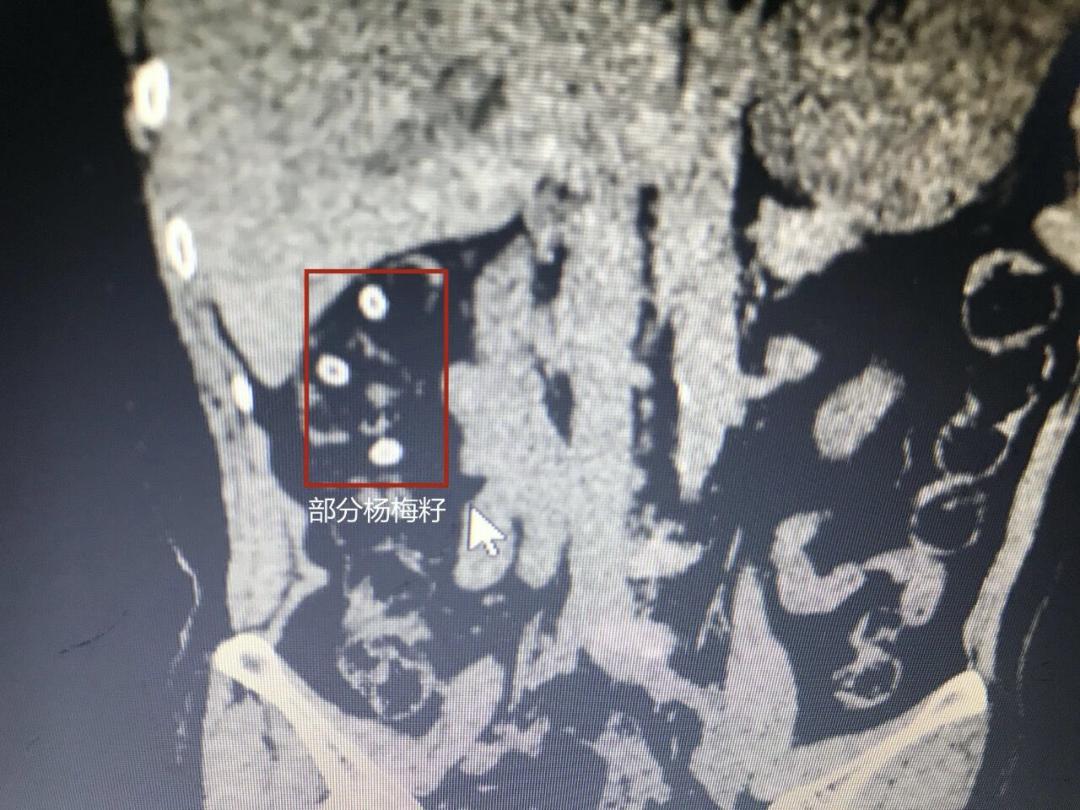

日前,我县一位60多岁的老人张大妈,因吃杨梅不吐籽出现腹痛症状赶到医院急诊室就诊。因她肚子比较痛,医生怀疑她是不是急性穿孔的急腹症,安排做了一个全腹部的CT。

CT显示,张大妈腹腔内有密密麻麻的九个的小点。医生询问后得知,果肉酸甜的杨梅是张大妈夏季最喜欢吃的水果,而且张大妈一直认为杨梅籽有清理肠道的功效,平常吃杨梅的时候习惯把杨梅籽吞下去。